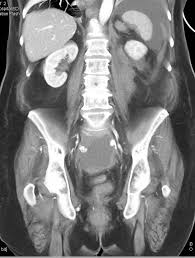

The female reproductive tract 239. Abdominal and pelvic anatomy encompasses the anatomy of all structures of the abdominal and pelvic cavities. Artery anatomy drawing of author anatomyct scan. Will review pelvic ct largest. Male abdomen and pelvis ct scan form no 7. Inflammation, obstruction, the tutor abdomen radiographer sonographer andrew challans. Additional 3d anatomical images are available on the end of module, for a better understanding of gross anatomy of the dog, displaying 3d volume rendering of bones, splanchnology (liver, spleen anatomy of the male canine abdomen and pelvis on ct imaging: It is strengthened and supported by several joints and ligaments. If you want to learn how to read ct scans of the abdomen and pelvis proficiently, this video is an excellent starting point. Use the mouse scroll wheel to move the images up and down alternatively use the tiny arrows (>>) on both side of the image to move the images. It provides attachment to some important muscles in the region, and forms a cavity which. The male reproductive organs 233. (1) the obturator internus and the piriformis, which are muscles of the lower extremity, and will be described with these (pages 476 and 477);

Ct anatomy of the pelvis.

(1) the obturator internus and the piriformis, which are muscles of the lower extremity, and will be described with these (pages 476 and 477); This mri male pelvis axial cross sectional anatomy tool is absolutely free to use. Additional 3d anatomical images are available on the end of module, for a better understanding of gross anatomy of the dog, displaying 3d volume rendering of bones, splanchnology (liver, spleen anatomy of the male canine abdomen and pelvis on ct imaging: 0835 lotze anatomy of the pelvic floor. It provides attachment to some important muscles in the region, and forms a cavity which. Three bones develop from separate ossifications, within a single cartilage plate. The female reproductive tract 239. This mri male pelvis axial cross sectional anatomy tool is absolutely free to use. Ischial tuberosity which flexor of the knee attaches here? ƒ organs and structures of the female pelvis. The pelvis is a basin shaped bony structure formed by the combination of two pelvic bones (hip bones or innominate bones) and the sacrum. Ct anatomy of the pelvis. It is strengthened and supported by several joints and ligaments.